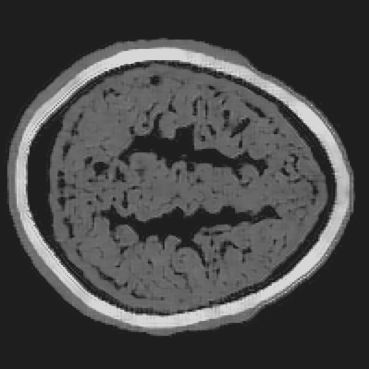

Refer to caption

(a) Partial-transducer dataset

(b) Full-transducer dataset

Figure 8: Stacked TRA Image with (a) Partial-transducer dataset and (b) Full-transducer dataset

To evaluate performance, we construct two acquisition setups from the same horizontal 2D slice of the phantom: (i) an idealized full-transducer dataset (Figure 4(b)) providing near-uniform coverage along the head contour, and (ii) a partial-transducer dataset (Figure 7) designed to reflect practical acquisition constraints. In the partial setup, a linear array with 51-element is repositioned around the head; for each view, the central element transmits and all other 50 elements receive. The partial setup includes 50 sweeps covering the full 360, meaning that for each sweep, the source and receivers rotate by 360/50=7.2360/50=7.2^{\circ}. Sweeping 50 views yields, per 2D slice, a channel tensor of shape (T,Ns,Nr)=(5001,50,50)(T,N_{s},N_{r})=(5001,50,50). The key distinction between these two datasets is their aperture: full-transducer provides near 360 coverage in a single placement, whereas partial-transducer attains coverage by aggregating neastest 50 receivers in a single placement, which is only around 36. Particularly, the partial-transducer setup includes only 50 sweeps, while the full-transducer setup uses all receivers covering the entire brain, with each transducer acting as a source in turn while the others serve as receivers. Compared to the full-transducer, the partial-transducer achieves coverage by combining a much smaller number of views. For each sweep, we generate the forward wavefield g(𝐱,t|𝐠){{g}}(\mathbf{x},t|\mathbf{g}) and the back-propagated wavefield p~(𝐱,t|𝐠)\tilde{{p}}(\mathbf{x},t|\mathbf{g}) and generate the TRA fragment with Eq. (7) (example in Figure 7). With the physical TRA method, the TRA fragment can be stacked to give the stacked TRA image. To validate the differences between the two datasets, we generated stacked TRA images using both datasets, as shown in Figure 8. As shown in Figure 8(b), the full-transducer dataset provides significantly greater detail in internal structures. Despite higher levels of noise and artifacts caused by the limited number of views, the partial-transducer dataset is still capable of capturing some meaningful tissue structures.